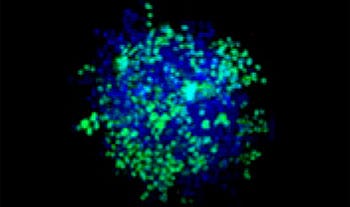

Making the spheroids transparent and imaging them with an FV3000 confocal laser scanning microscope enabled us to image the co-cultured cancer spheroids at depth. Staurosporine treatment increased the number of dead cells in a dose-dependent manner (Fig. 2*1). Three-dimensional analysis is required to determine which cells are dead and how many dead cells there are in a three-dimensional mass.

Figure 2. Drug response in co-culture spheroids

Figure 2. Drug response in co-culture spheroids*1

The Hoechst33342 signals enabled us to recognize the nuclei. All cells were classified into two groups based on the presence or absence of an EGFP signal—EGFP positive (HeLa cells) and EGFP negative (A549 cells). The cells in these two groups were further divided according to the presence or absence of dead cell signals (TO-PRO3, red) for a total of four groups (Fig. 3*1). The percentage of live to total cells of both A549 and HeLa cells was calculated and plotted (Fig. 4). The results showed that HeLa cells were more sensitive to staurosporine than A549 cells.